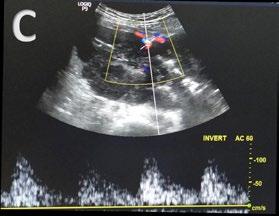

In contrast to acute complications, chronic complications are generally more unique to the Caesarean section itself, and are not typically seen with other surgical procedures, with the exception of incisional hernia. Caesarean scar niche was identified as an important cause of pain and irregular bleeding (Figure 1).

C-section: Caesarean section; US: ultrasound.

A B C D E F G H J K L M I Abstract ● ECR 2024 Creative Commons Attribution-Non Commercial 4.0 ● April 2024 ● Radiology 23

Figure 1: Caesarean scar niche.